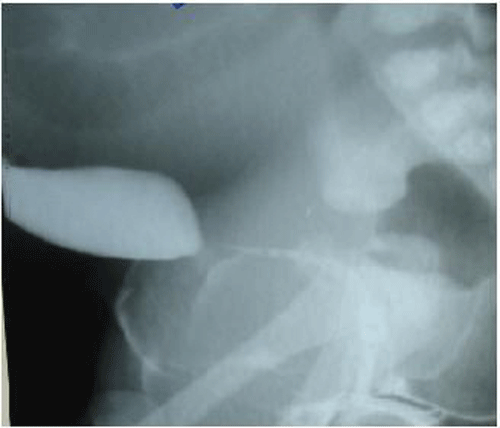

A large abdominal mass displacing the bowel to upper abdomen was seen on plain abdominal radiograph. Ultrasound and CT scan findings (Fig. 2a and 2b) were consistent with the huge HMC compressing rectum and bladder. There was associated bilateral hydroureteronephrosis on CT scan. There was no communication between the bladder and vagina on genitogram (Fig. 3), which was done postoperatively. Neonatal cystoscope was not available at our centre to establish this finding. Echocardiography showed ASD. A cutaneous vaginostomy was created and Foleys catheter left in situ for 10 days. The neonate had an uneventful recovery and from postoperative day 1 baby started passing stools. Child is now thriving well and is 1 year old. She has been planned for definitive surgery.

Figure 3: Genitogram shows no communication with vagina and urinary system.